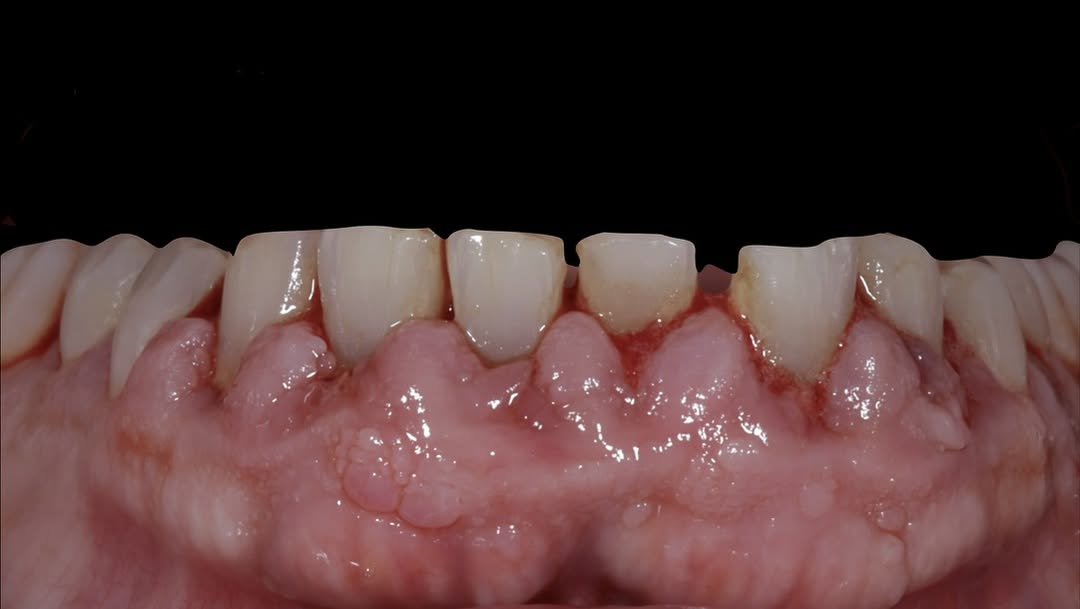

Se presenta un caso clínico de restauración directa en resina composite, ejemplo del valor de la precisión y la técnica meticulosa incluso en procedimientos considerados rutinarios dentro de la práctica diaria. El caso pone en evidencia la importancia del control de la morfología, la textura y la integración cromática, así como del adecuado aislamiento del campo operatorio y la estratificación del material, factores determinantes para conseguir un resultado natural, funcional y duradero. A través de una ejecución cuidadosa, se logró una restauración estéticamente imperceptible y funcionalmente estable, que respeta los principios de mínima invasión y adhesión efectiva. Este tipo de procedimientos, aunque cotidianos, reflejan la constancia y el nivel de exigencia clínica necesarios para ofrecer odontología de calidad en todos los casos, independientemente de su complejidad.

Durante una mañana, asistirás a una Cirugía Mucogingival de recubrimiento radicular de recesiones múltiples en IV y V sextante (36 a 43).

Aprende la planificación y técnica de la cirugía Mucogingival para el recubrimiento de recesiones y aumento de banda queratinizada en el sector anteroinferior